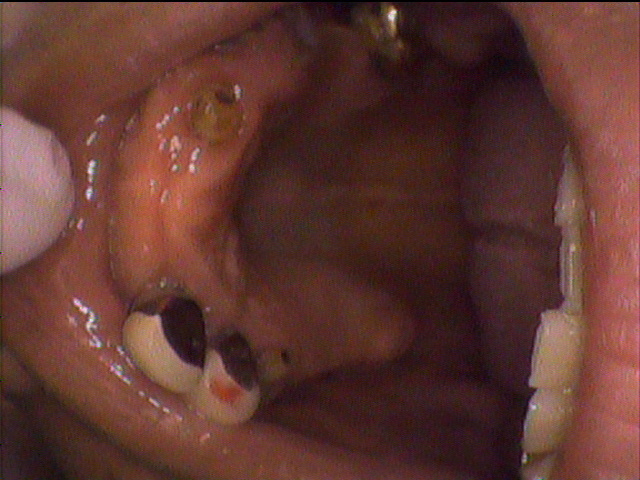

本日、出来上がりました自費の部分入れ歯ー下顎メタルプレートの症例です。

81歳の女性OUさんはとけも若々しいかたで、上下ともに、ぶぶん入れ歯ですが、今回は下顎の左右の奥歯のメタルプレートの入れ歯を新しく作りました。

自費によるメタルプレート義歯で、薄く丈夫な義歯として、とても舌感の良好な状態にすることができ、さらに自由な義歯の設計ができるため、残っているはにかける針金は白金加金で作成し、残存歯にやさしい設計となっており、舌に触れるバー部分はコバルトクロム合金で、丈夫に薄く作ってあります。

(参考代金;30万円)